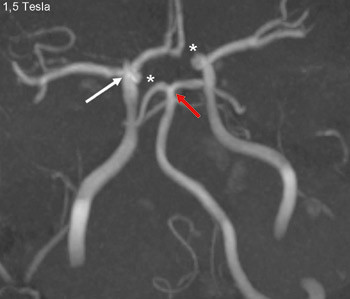

Figure 3

A person in his 20s with known migraine with aura developed infarcts in the right middle cerebral artery and both anterior fields of supply (Figure 1 shows a magnetic tomography diffusion weighted series). Cerebral computed and magnetic tomography with magnetic resonance angiography (MRA) after admission showed normal blood flow and no sign of dissection or vasculitis. Hemicraniectomy became necessary after development of malignant cerebral oedema. MR angiography the first postoperative day showed open arteries (Figure 2 shows an open carotid top (white arrow), normal basilar top (red arrow), and a non-closed circle of Willis, an anatomically normal variant (stars). Testing for illegal drug use, anticardiolipins, anti-nuclear antibodies, neurone antibodies and tumour markers was negative. Transoesophageal echocardiography showed a minimally patent foramen ovale, according to a cardiologic evaluation unlikely to be related to the episode. The patient developed severe brain stem involvement and MR angiography showed narrowing of the posterior branch of the basilar artery (arrows in Figure 3). Arterial vessel spasms were suspected retrospectively. The first suspected vessel spasm, in the right – middle/anterior branch, remained undocumented. The second, in the posterior branch of the basilar artery, was documented postoperatively (arrows in Figure 3). Images of several newly developed infarcts in the posterior circulation are not shown. Three weeks after the hemicraniectomy the angiogram was normalised (Figure 4).